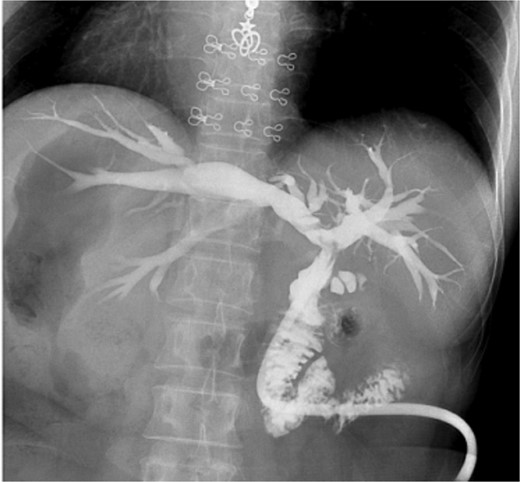

The patient, a 56-year-old female, was admitted on July 7, 2024, with a one-day history of abdominal pain and fever. The pain, which began on July 6 after consuming greasy food, was paroxysmal and located in the upper abdomen, accompanied by chills and a fever as high as 39°C. CT imaging revealed common bile duct stones and post-cholecystectomy status. Physical examination upon admission showed jaundice, with mild tenderness in the left upper quadrant, without rebound tenderness, and a negative Murphy’s sign. MRI and MRCP of the upper abdomen revealed bile duct dilatation due to a 26 mm stone in the distal common bile duct, with mirror-image arrangement of the internal organs (Figs. 1 and 2). The diagnosis was choledocholithiasis with cholangitis and situs inversus totalis. After completing preoperative evaluations, the patient underwent laparoscopic common bile duct exploration, choledochotomy for stone extraction, choledochoscopy, T-tube drainage, and lysis of adhesions under general anesthesia on July 9, 2024.

MRI shows a 26 mm stone in the distal common bile duct with bile duct dilation.